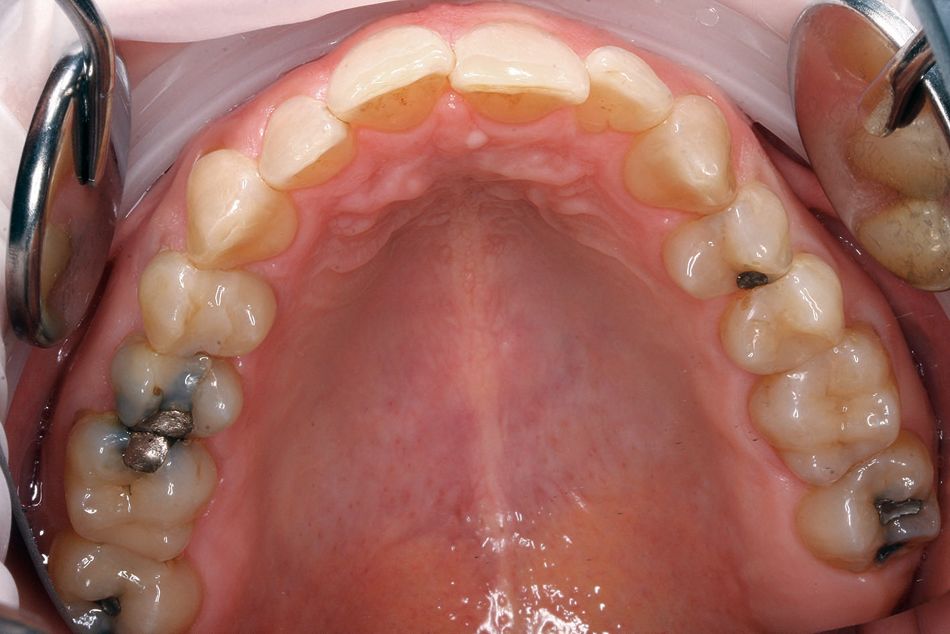

Abb. 1a bis 1f: Behandlung eines linksseitigen Kreuzbisses bei einer geringfügigen Rückenlage des Unterkiefers mit 20 Schienenpaaren

(Abbildungen: Komischke)

KOMISCHKE: Wir haben viele Patienten mit Okklusionsstörungen, wie bukkale Nonokklusionen und Kreuzbiss einzelner Zähne. Behandelt man dies nicht, sind die CMD vorprogrammiert. Das Fallbeispiel (Abb. 1a bis 1f) zeigt das klinische Outcome.